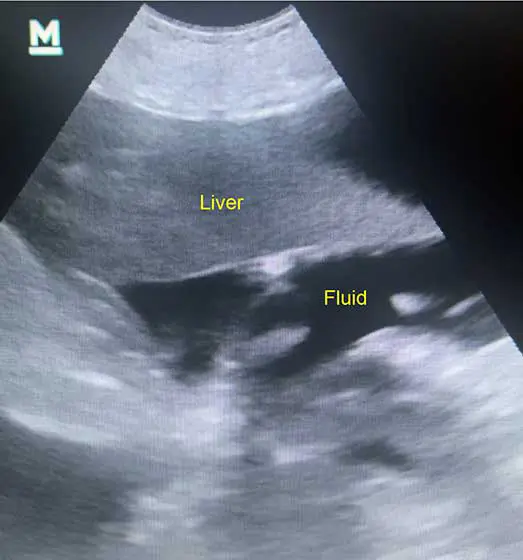

Abdominal ultrasound showing small volume of abdominal free fluid.

A point-of-care ultrasound, if available, should be readily performed. Free fluid shows as hypoechoic or anechoic regions, with small volumes located most commonly cranial to the liver or caudal to the bladder.